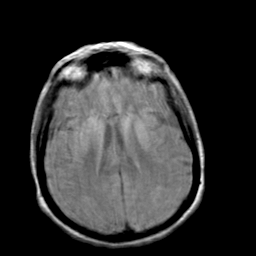

Creutzfeld-Jakob disease: proton density-weighted MR -- Slice #14

[Home][Help][Clinical] Slice 14